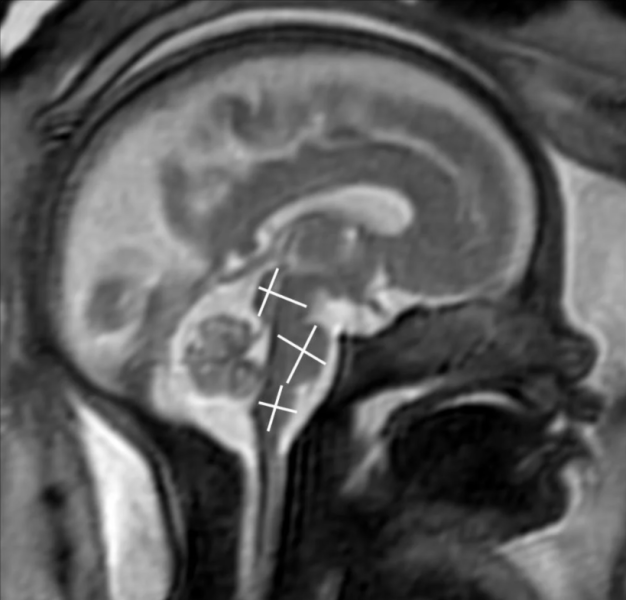

This photo gallery shows the variety of radiological presentations of COVID-19 (SARS-CoV-2) in medical imaging, including computed tomography (CT), radiograph X-rays, ultrasound, echocardiograms and magnetic resonance imaging (MRI). The radiology images show examples of typical COVID pneumonia in the lungs and the numerous complications the virus causes in the body in multiple organs, including the brain, kidneys, heart, abdomen and vascular system.

Ultrasound, especially hand-held ultrasound imaging devices, have become a primary imaging modality for novel coronavirus because of the ease to bag the device and sterilize it after use. CT and mobile X-ray systems are also used as front-line imaging systems for COVID-positive or suspected COVID patients.